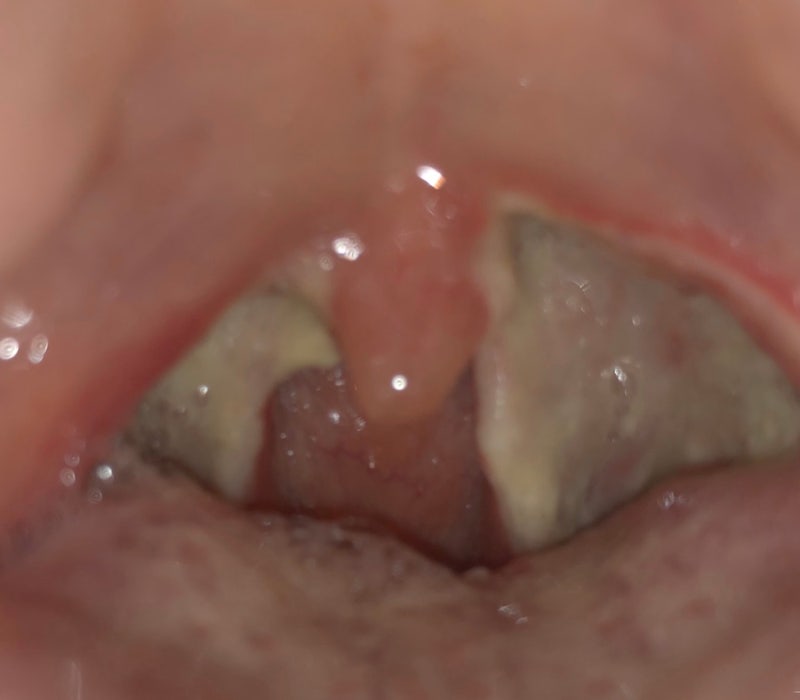

편도절제술(5~6일차) 리뷰

* 11/20(일) 편도수술 7일차 요약: 수술 첫날급 통증 하루종일 한것: 냉찜질

새벽에 일어났는데 당황하다. 이 고통 먼데. 아이스팩이 녹아서 온찜질하듯 뜨거웠다. 도대체…뭐지…?침을 삼켰을 때 통증이 수술 당일의 그것과 같았다. 그래서 최대한 삼키지 않으려고 하는데 한 번씩 넘길 때마다 머리가 짜릿하다. 아이스팩 교환해주니까 그래도 살 수 있겠네. 그렇다고 죽을 정도는 아니다. 네가 선택한 편도 수술이야. 악으로 배짱으로 버텨라… 하지만 예고도 없이 찾아온 아픔에 당황한다. 시원한 죽 먹자.

아침에 일어났더니 너무 아팠어.ㅠㅠㅠㅠㅠ 시험삼아 약이랑 아이스크림 먹었어 ㅠ

저녁까지 목이 부어 있었다. 얼음물을 마셨다. 편도수술 희망편인줄 알았는데 후발주자였다. 그런데 입천장이랑 입안은 왜 화상을 입었을까? ?